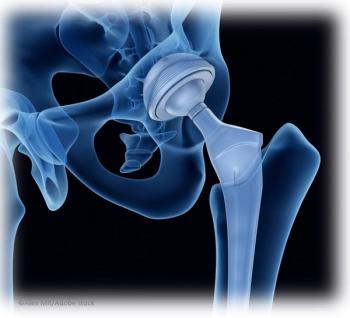

Investigators report a 30% reduced risk of total joint replacement in persons with type 2 diabetes treated with metformin vs those who did not receive the drug.